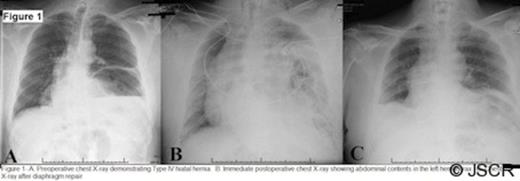

A 60 year old man with a muscular habitus and a remote history of reflux treated with an open Nissen Fundoplication 20 years prior, presented with an asymptomatic type IV paraoesophageal hernia (Figure 1A). Intraoperative findings confirmed that the stomach, transverse colon, and omentum were in the chest. The hernia was reduced and the hiatal defect was repaired primarily with multiple simple 1-0 Silk sutures. The previous Nissen repair was intact, and his oesophageal length was adequate and without tension. For these reasons, a Collis-gastroplasty was not performed. The addition of mesh reinforcement was considered, but given the well placed sutures and concerns of complications with mesh, this was decided against. He tolerated extubation well, and was transferred to the recovery room.

Soon after arriving in recovery, he began to experience significant respiratory distress. A chest x-ray revealed diffuse left sided air-filled opacities (Figure 1B). He was taken to the operating room urgently for re-exploration with the concern that he re-herniated through his hiatal closure. He was found to have abdominal contents in the chest through a large anterolateral diaphragm rupture from the chest wall. The previous primary paraoesophageal repair was clearly intact. A tension free repair of the diaphragmatic tear was completed with an 18 x 24 cm piece of Gore DualMesh® anchored to diaphragm edge and to the 8th and 9th ribs, using horizontal mattress stitches with 2-0 prolene suture (Figure 2). He was transferred to the ICU in critical condition, and he subsequently experienced a prolonged and complicated ICU course. He required prolonged ventilator support and was extubated thirteen days later. He developed atrial fibrillation and acute renal failure that required hemodialysis. He had a Barium oesophagogram that showed normal position of this stomach and a patent gastro-oesphageal junction, and he was eventually transferred to a rehabilitation facility, and later home. A chest x-ray after full recovery shows a raised left hemi-diaphragm (Figure 1C).